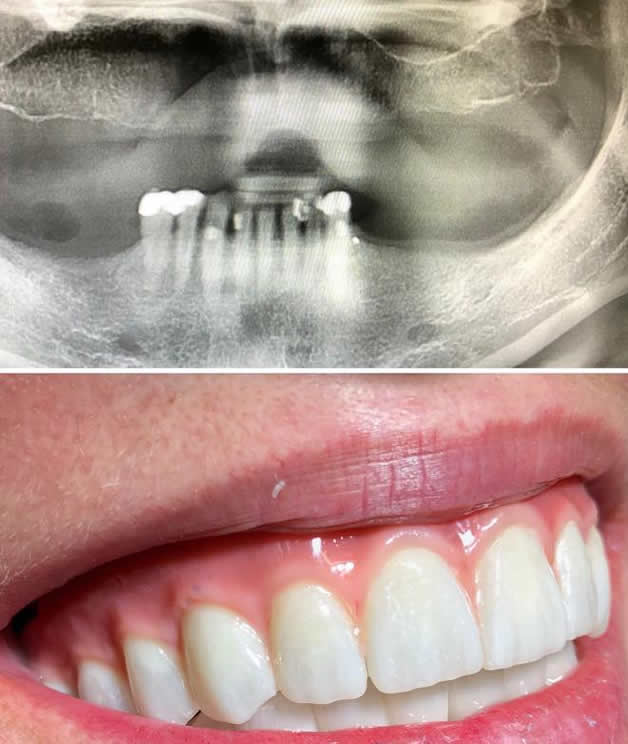

All on 6 je cjelokupno  protetsko rješenja koje se sastoji od 6 implantata koji su nosači zubnog mosta.

Sustav je jednak kao i kod All-on-4 a najviše se upotrebljava u gornjoj čeljusti gdje se postavljaju dva implantata više radi meke kosti koja prevladava u gornjoj čeljusti.

All-on-6 sustav pruža veću stabilnost i nosivost u odnosu na All-on-4, čime je posebno pogodan za pacijente s većim funkcionalnim zahtjevima. Most izrađen modernim tehnologijama nadoknađuje ne samo zube nego i oblik zubnog grebena, omogućujući visoku estetiku i prirodan izgled. Održavanje higijene je jednostavno zahvaljujući pristupačnom dizajnu, a sustav osigurava dugoročnu čvrstoću, stabilnost i trajnost.

Jednako kao i kod All-on- 4 prednost ovakve vrste mosta je što osim zubi nadoknađuje i nepravilan zubni greben, te je zbog materijala od kojeg se izrađuje lakši od klasičnog mosta na implantatima, a puno čvršći i kompaktniji od proteze. Također ga odlikuje izrazito dobra mogućnost čišćenja i održavanja higijene.